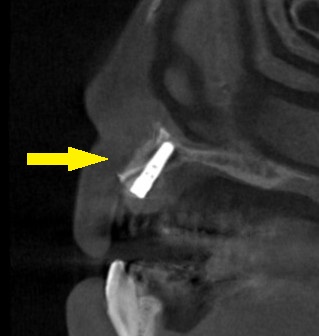

そこでインプラント埋入と同時に、口唇側に人工骨を補填して、骨の厚みを増やす骨造成術を併用することで、インプラント治療が可能であると提案させていただきました。

この手術方法で、同意が得られましたので、本日、インプラント埋入と同時骨造成術を行いました。

下の写真が、手術前後のCTです。